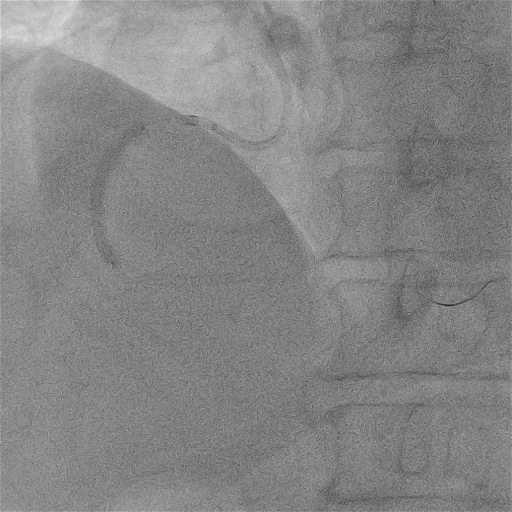

我院左冠基础造影

造影示:LM:(-);LAD:中段及远段轻度狭窄伴钙化;LCX:远端向RCA发出侧枝。

我院右冠基础造影

RCA:全程弥漫多处95%以上狭窄伴重度钙化,最重处次全闭塞,血流TIMI2级。